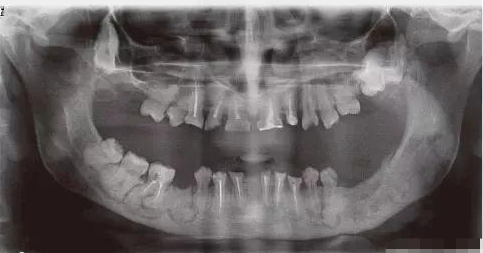

他是一个年轻的父亲,还患有罕见病——巨大牙骨质瘤,全世界患此病症的,不到10人。

肿瘤长在他的上下颌骨处,反复引发牙骨化脓病变,最终导致颌骨的肿胀、面部严重畸形。

经过多次手术,李永学只剩下一颗臼齿,就是我们俗称的大牙。他也因此被称为“臼齿爸爸”。

出生6个月后,女儿也被诊断为巨大牙骨质瘤症,肿瘤大到嘴巴无法闭合,脸部严重畸形。

而且这种病无法根治,只能定期接受肿瘤切除手术,以矫正畸形。